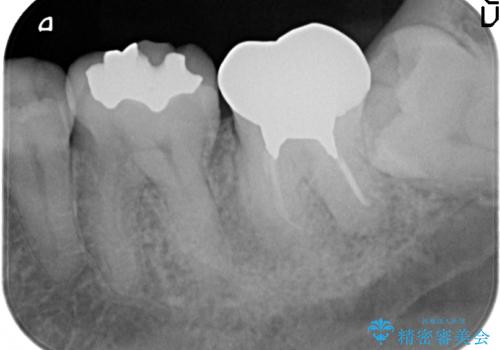

- 奥歯の痛みを主訴に来院された患者様です。

精査したところ、ブリッジの支台歯となっている左下の奥歯(左下7)は大きなう蝕により神経が死んでいました。

根管治療後、メタルボンドブリッジによる補綴治療を行いました。